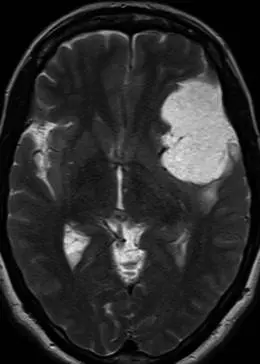

一名49岁患者,经病理证实为3级(间变性)脑膜瘤。A(平扫头颅CT):显示右侧额叶巨大占位性病变,密度不均,周围伴血管源性水肿,并导致明显占位效应。B(横轴位T2加权MRI):肿块呈不均匀信号强度,周边可见相对于高信号核心的厚壁低信号环。C(增强后MRI):强化肿块内部可见中央强化减低区,提示存在中央坏死。D(灌注加权MRI):相对脑血容量(rCBV)未见升高。